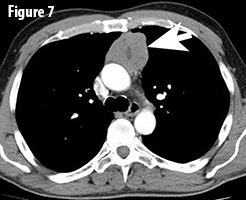

Thymomas are rare epithelial neoplasms of the anterior mediastinum (Figure 7, arrow). They are the most common mediastinal tumors in

adults with an incidence of 1-5 / million population / year. Thymomas often behave indolently, but are considered to be malignant neoplasms given their potential for aggressive local growth, recurrence, metastasis and potentially even might lead to the death of the patient. It is important to distinguish thymoma from thymic carcinoma, which has an overall worse outcome. Approximately 40% of patients with thymoma have a paraneoplastic or autoimmune syndrome of which myasthenia gravis is the most common. Conversely, 15 to 21% of patients with myasthenia gravis have a thymoma. These syndromes can even be the initial presenting factor as in this case. The prognosis of thymomas is mainly affected by margin status and tumor stage (TNM stage); histologic subtype is also associated with prognosis.